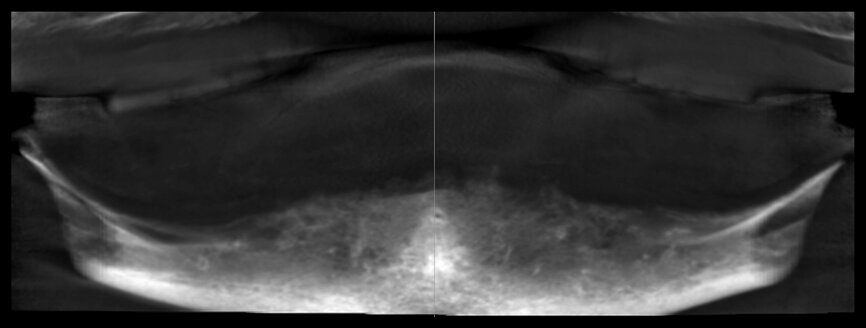

The original treatment plan conceived by the original treating dentist was to place four narrow-diameter implants in the anterior mandible to support the existing complete denture with overdenture attachments, due mostly to financial limitations of the patient. A flapless surgical protocol was chosen, and the initial implant site located by the panoramic radiograph.

The panoramic reconstructed view of the edentulous mandible may provide the clinician with some information regarding the bony anatomy, but it is not sufficient to plan for implants in the majority of case presentations. It is essential to precisely locate the bilateral anatomical sites where the inferior alveolar nerve exits the mandible, and the panoramic radiography cannot provide this information accurately. To plan for the placement of implants, it would be important to understand the available bone anatomy to determine the number of implants that could be placed, and the diameter and lengths required. The 2-D panoramic radiograph cannot predict the width, trajectory,

or density of the bone, as well as the thickness of the overlying soft tissue. Therefore, it can be difficult for a clinician to make truly educated decisions based on two-dimensional imaging modalities.